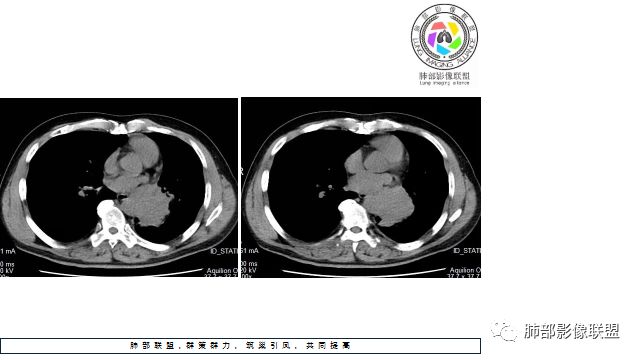

1.左下肺门区巨大肿块,支气管显示不清,轻度阻塞性炎症,没有明显肺不张,提示管腔受压狭窄可能性大于堵塞,这较少见于鳞癌。

2.病灶边缘光滑,未见明显分叶、毛刺,未见明显强化,这符合腺癌影像学特点,却符合神经内分泌癌表现。

3.病灶内密度均匀,轻到中度均匀强化,大病灶未见明显液化坏死区及空洞,不符合鳞癌而符合小细胞肺癌特点。

4.病灶内有肺动脉走形,血管局部受压,未见破坏,病灶乏血供,呈血管包埋或血管造影征;侵袭性力强及破坏力弱、血管漂浮都符合SCLC,所以鳞癌的可能性也不大。

5.左肺门块影或淋巴结肿大,竭力挤兑肺门血管结构,呈冰冻肺门;有时候SCLC可以单独呈现冰冻肺门,而没有没有冰冻纵隔。